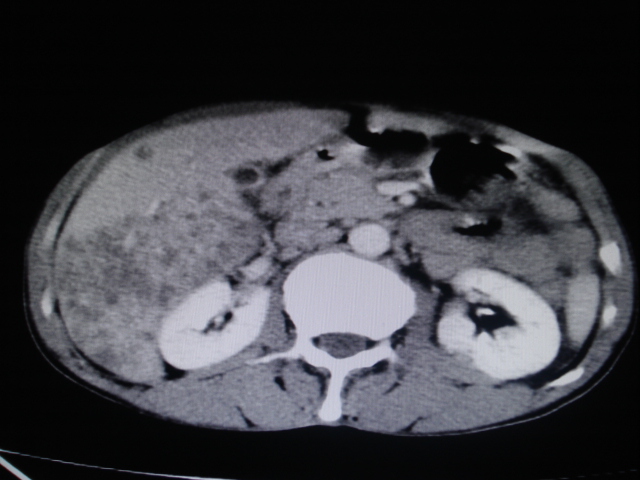

标题: CT24041:肝脏占位,请会诊!

男性,62岁。肝右叶占位,平扫及增强如下,延迟期为15分钟扫描。